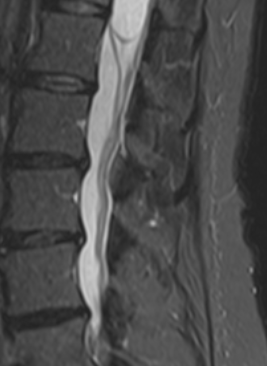

Les investigations menées par la suite ont permis la découverte d'un kyste médullaire épendymaire (bulle remplie de liquide située dans la moelle épinière). Sur une période de 5 mois, quatre interventions chirurgicales ont été réalisées, incluant l’installation d’une valve destinée à contrôler l’écoulement du liquide céphalo-rachidien (liquide protégeant le cerveau et la moelle épinière). Cette dernière permit, il y a quelques mois, de réduire considérablement la taille d'un kyste sans avoir recours à une chirurgie.